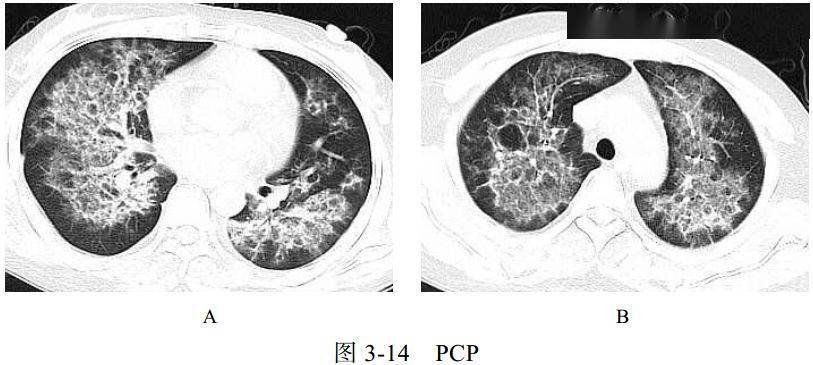

五、与肺孢子虫感染的鉴别诊断

卡氏肺孢子虫肺炎(PCP)是艾滋病患者最主要的机遇性感染之一。卡氏肺孢子虫引起Ⅰ型肺泡上皮细胞损害、Ⅱ型肺泡上皮细胞增生和间质性肺炎等病理改变,可导致肺间质性纤维化。临床表现为进行性呼吸困难、咳嗽、发热,病程持续数周或数月。PCP 相关检测查找卡氏肺孢子虫病原体。艾滋病患者免疫力极低,常合并其他感染,如结核、真菌等

影像学表现:

(1)广泛或局限性磨玻璃样密度影,以肺门周围为主,有融合趋势(图 3-14A)

(2)慢性及复发的病例可引起小叶间隔增厚及网格影

(3)可出现囊性病变(图 3-14B)、自发性气胸及肺实变影

(4)常不伴肺门及纵隔淋巴结肿大和胸腔积液